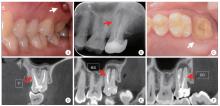

Figure 2

Clinical images and postoperative periapical radiograph illustrating the microscopic removal of the fractured instrument, perforation repair and root canal filling for left maxillary second molar A, fractured instrument tip observed in the mesiobuccal canal (red arrow) under dental microscope; B, instrument becomes loose (red arrow) after ultrasonic vibration; C, the retrieved 2.5 mm instrument segment; D, post-retrieval PA shows 2 mm residual in the apical region (red arrow); E, a lateral perforation is visible in the mesiobuccal canal near the furcation area after instrument retrieval (red arrow); F, the apical portion of the mesio-buccal canal is filled with gutta-percha (red arrow); G, the perforation is repaired with iRoot BP bioceramic material (red arrow); H, postoperative periapical radiograph confirms flush filling and a well-sealed perforation repair. MB, mesiobuccal."